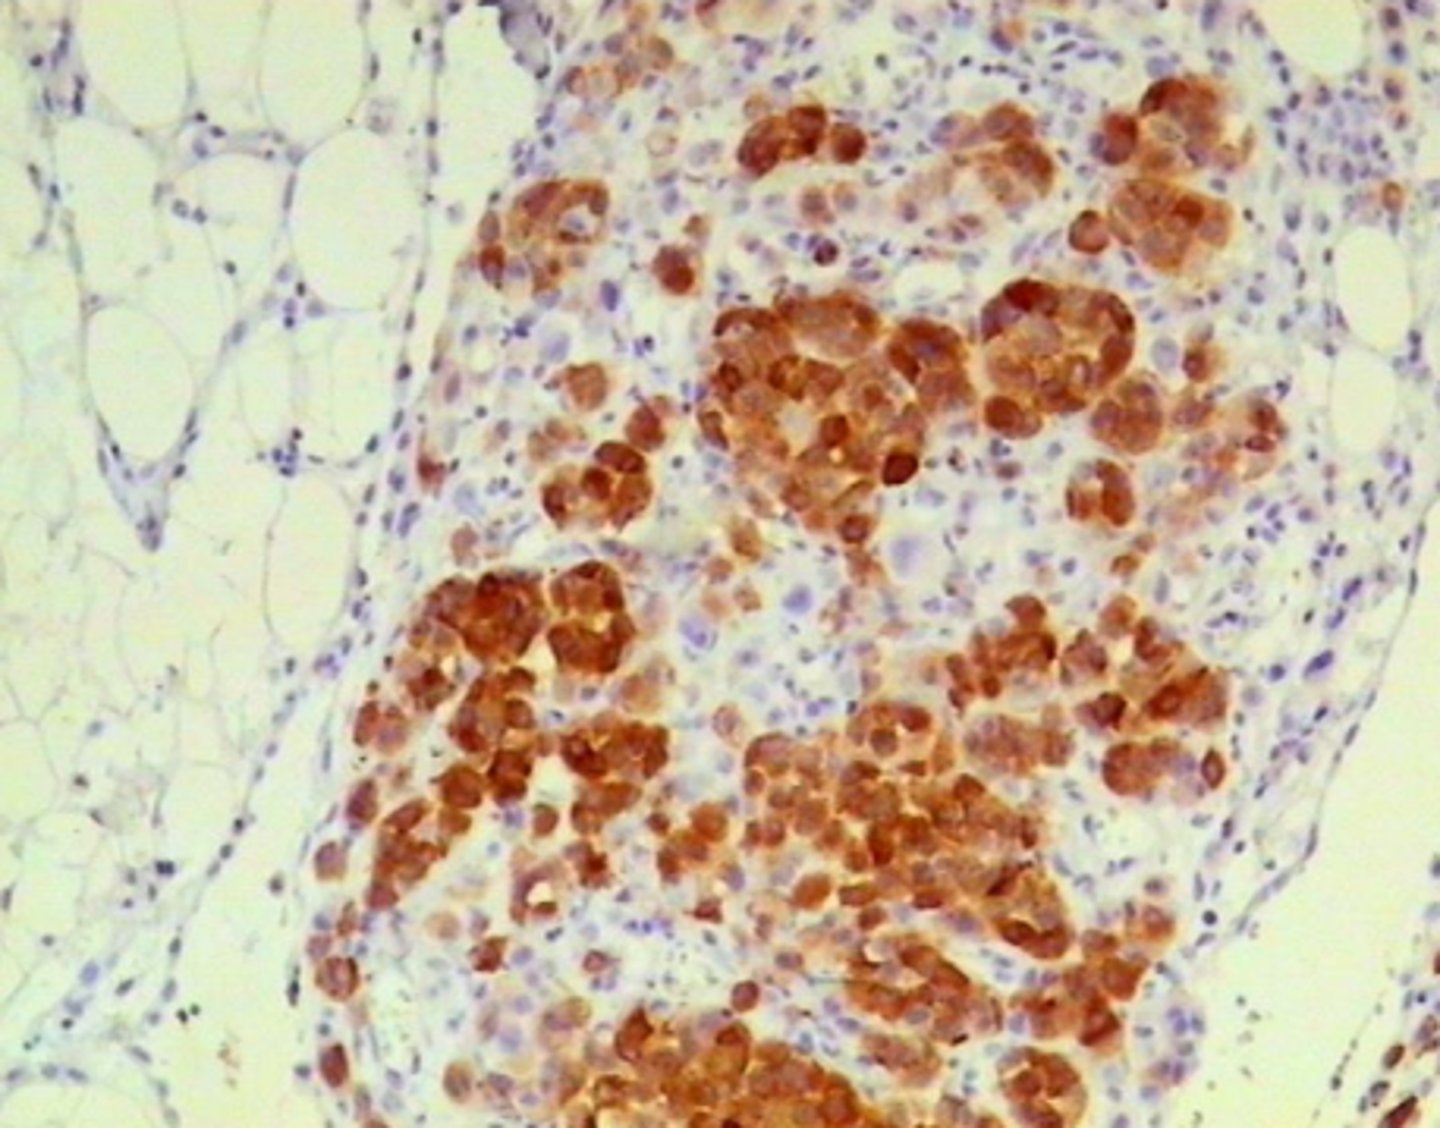

Melanomas metastāze taukaudos (omentā)

Melanomas metastāze taukaudos (omentā): melanosomu proteīna HMB-45 ekspresija